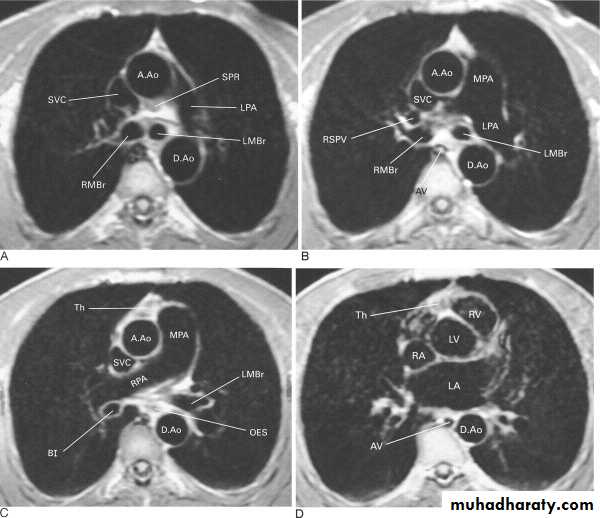

MRI